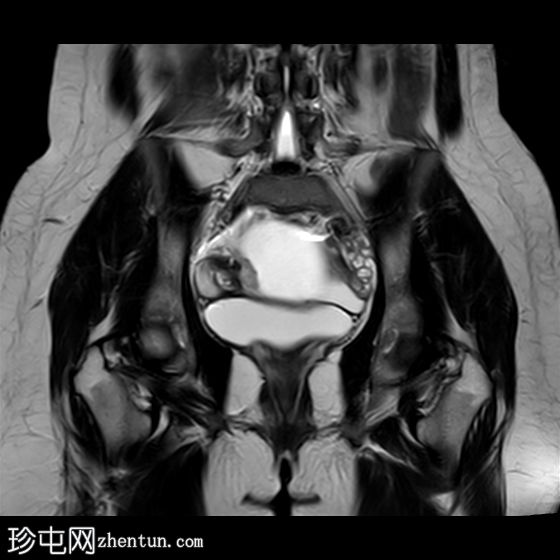

冠状位

T2加权像

右侧卵巢增大,卵泡呈周边排列。

附件血管蒂扭转(漩涡征)。

右侧附件旁可见一较大的、边界清晰的盆腔囊性病变,向右倾斜,提示为卵巢旁囊肿。

本病例展示了卵巢扭转的典型影像学特征,包括卵巢增大、卵泡呈周边移位、卵巢向内侧偏移以及特征性的漩涡征。

在这种情况下,较大的卵巢旁囊肿被认为是发生卵巢扭转的高危因素。如果卵巢旁囊肿较大(>5厘米)或活动度较大,其重量/活动度增加会牵拉附件,导致卵巢和输卵管发生扭转。